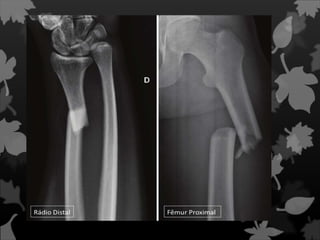

Fraturas de Smith e

Colles

Fratura que acomete a parte

distal do rádio.

Fratura de Galeazzi

Uma fratura de

Galeazzi é

uma fratura da região

distal do rádio com

ruptura da membrana

interóssea e da

ligação com a ulna,

com subluxação da

ulna.

Fraturas de Smithe Colles Fratura que acomete a parte distal do rádio.

Fratura de Galeazzi Umafratura de Galeazzi é uma fratura da região distal do rádio com ruptura da membrana interóssea e da ligação com a ulna, com subluxação da ulna.